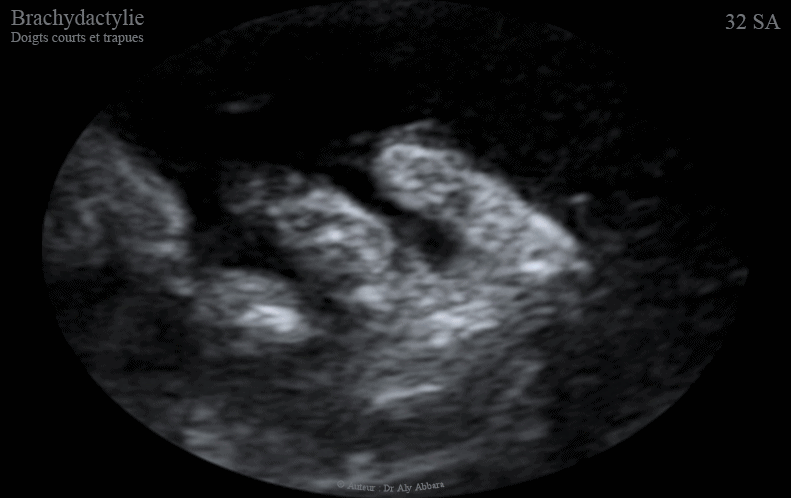

Images échographiques en 2D et en 3D montrant l'aspect ultra-sonre d'une brachydactylie : doigts courts et également trapues (larges et courts.

Ce signe fait partie des anomalies mineures parfois retrouvées en cas de trisomie 21 (comme c'est la situation, dans le cas présenté dans cet article).

• Dans la trisomie 21, les mains peuvent être trapues (courte et larges).